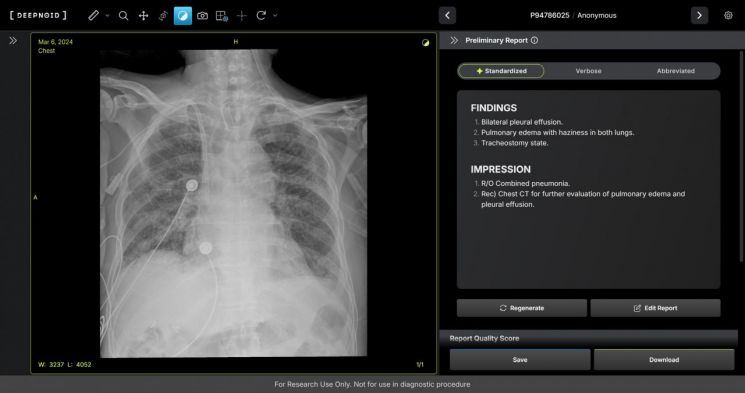

M4CXR은 흉부 엑스레이 영상에서 41종의 병변을 판독해 수초 만에 일관성 있고 신뢰성 높은 판독소견서 초안을 작성한다. 흉부 엑스레이 영상과 대응되는 1000만건 이상의 판독소견서 데이터를 학습해 구현한 기술로 응급상황에서 의료진이 즉시 예비 판독 결과를 받을 수 있다. 중요한 임상 결정과 환자 진료에 더욱 집중할 수 있도록 지원하며 영상의학과 전문의의 판독을 보조한다.

휴먼영상의학센터 김성현 원장은 "흉부 엑스레이는 임상 현장에서 가장 빈번하게 시행하는 검사지만 판독 의사의 부족으로 판독 속도에 한계가 있었다"고 설명했다. 이어 "증가하는 영상 판독 수요 속에서 응급상황에서도 의뢰와 동시에 예비 판독 결과를 의료진에게 전달할 수 있을 것"이라며 "진단의 신속성을 높이고 영상의학과 전문의의 판독을 보조해 정확성을 높이는 데 기여할 것으로 기대한다"고 말했다.

김 원장은 "거대 언어모델(LLM) 기반 생성형 AI로 만들어지는 영상의학 판독 솔루션이라는 점에서 기존 신경망 모델 한계를 뛰어넘는 제품이 될 것이라는 점에서 의미가 크다"고 덧붙였다.